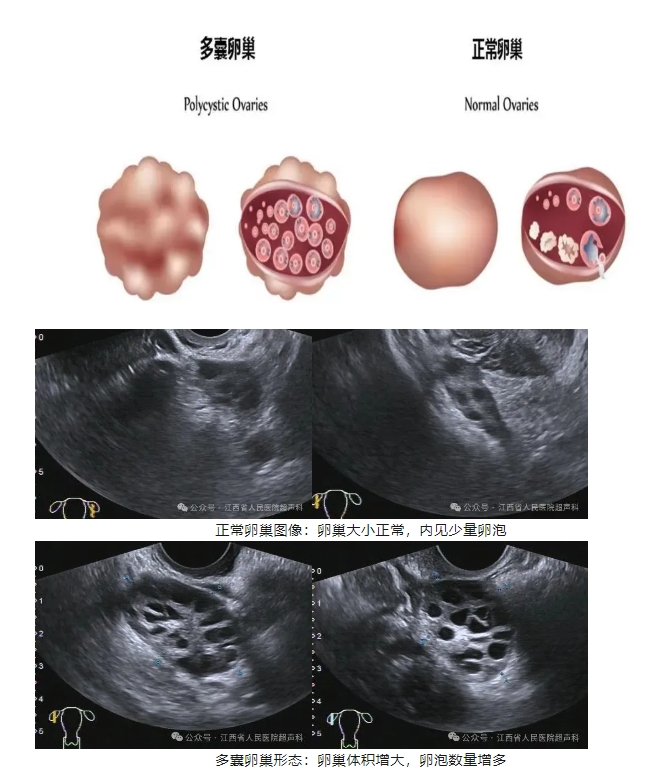

2.超声表现

超声主要表现为卵巢多囊样改变,又称多囊卵巢形态(polycystic ovary morphology,PCOM):

(1)超声可见双侧卵巢均匀性增大,体积大于10cm³(卵巢体积简化计算公式:V=0.5x长x宽x高)。

(2)卵巢包膜增厚,回声增强。

(3)卵巢内见多个小卵泡回声,直径约2-9mm,规律排列于卵巢包膜下方,同一超声切面,其卵泡数量≥12个。

(4)卵巢髓质部分回声增强。

(5)经超声连续监测未见成熟卵泡生成,无排卵现象。

3.病理表现

其病理特点表现为双侧卵巢明显增大,表面凹凸不平,卵巢包膜较正常增厚约2~4倍,其内富含血管结构;卵巢剖面可见大量卵泡规则排列于卵巢包膜下方,直径约2-9mm,少数卵泡可散在分布于卵巢皮质层内。